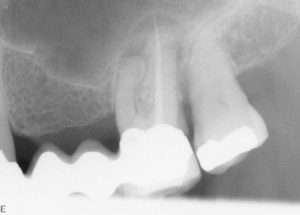

Clinical Cases